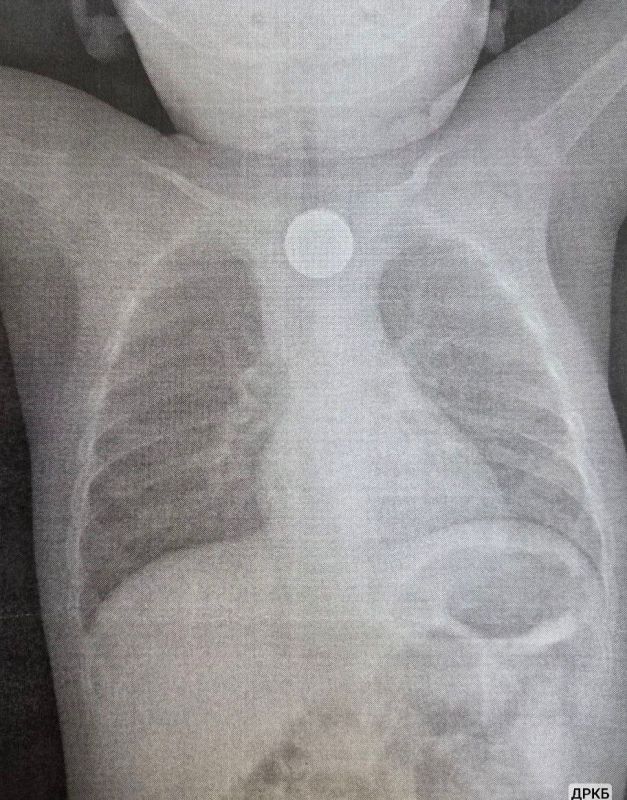

К счастью, врачи ДРКБ смогли вовремя извлечь инородные тела: кроме батарейки малыш проглотил также монету. Ребенок поступил с высокой температурой, рвотой и хрипами при дыхании. Осмотр выявил неизвестное инородное тело, из-за которого ему стало плохо....